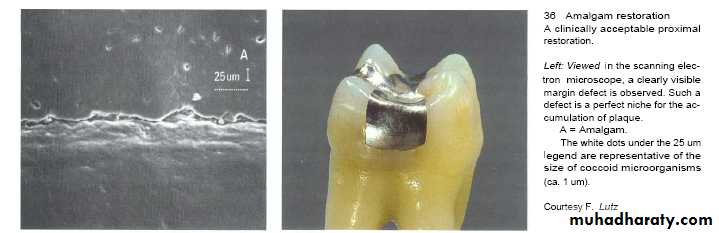

Roughness of restorations is the main cause of plaque accumulation and subsequent inflammation which is caused by:-

4- Inadequate marginal fitness of restoration.

The rougher the surface of the restoration subgingivally, the greater the plaque accumulation and gingival inflammation.

Regardless of the restorative material selected, a smooth surface is essential on all materials which are subgingivally placed.